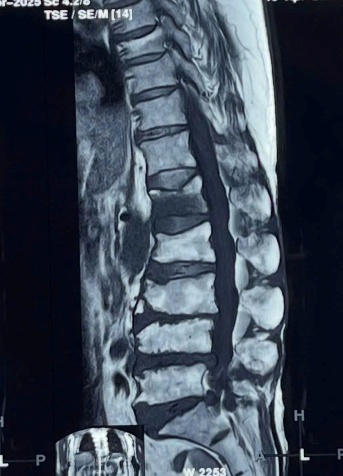

2.3. Điều trị bệnh lý cột sống: với sự hỗ trợ chuyên môn của Bệnh viện Chợ Rẫy, Bệnh viện Nhân Dân 115 TpHCM, Khoa đã và đang thực hiện phẫu thuật các trường hợp bệnh lý cột sống thắt lưng như: gãy cột sống; lấy nhân đệm thoát vị đơn thuần, qua kính vi phẫu; phẫu thuật trượt đốt sống; bơm xi-măng điều trị xẹp đốt sống do loãng xương;…Điều trị nội ngoại khoa các trường hợp Viêm thân sống đĩa đệm.

Phẫu thuật cột sống với sự hỗ trợ chuyên môn tuyến trên

Trước mổ

Sau mổ

Phẫu thuật lấy nhân đệm qua kính vi phẫu